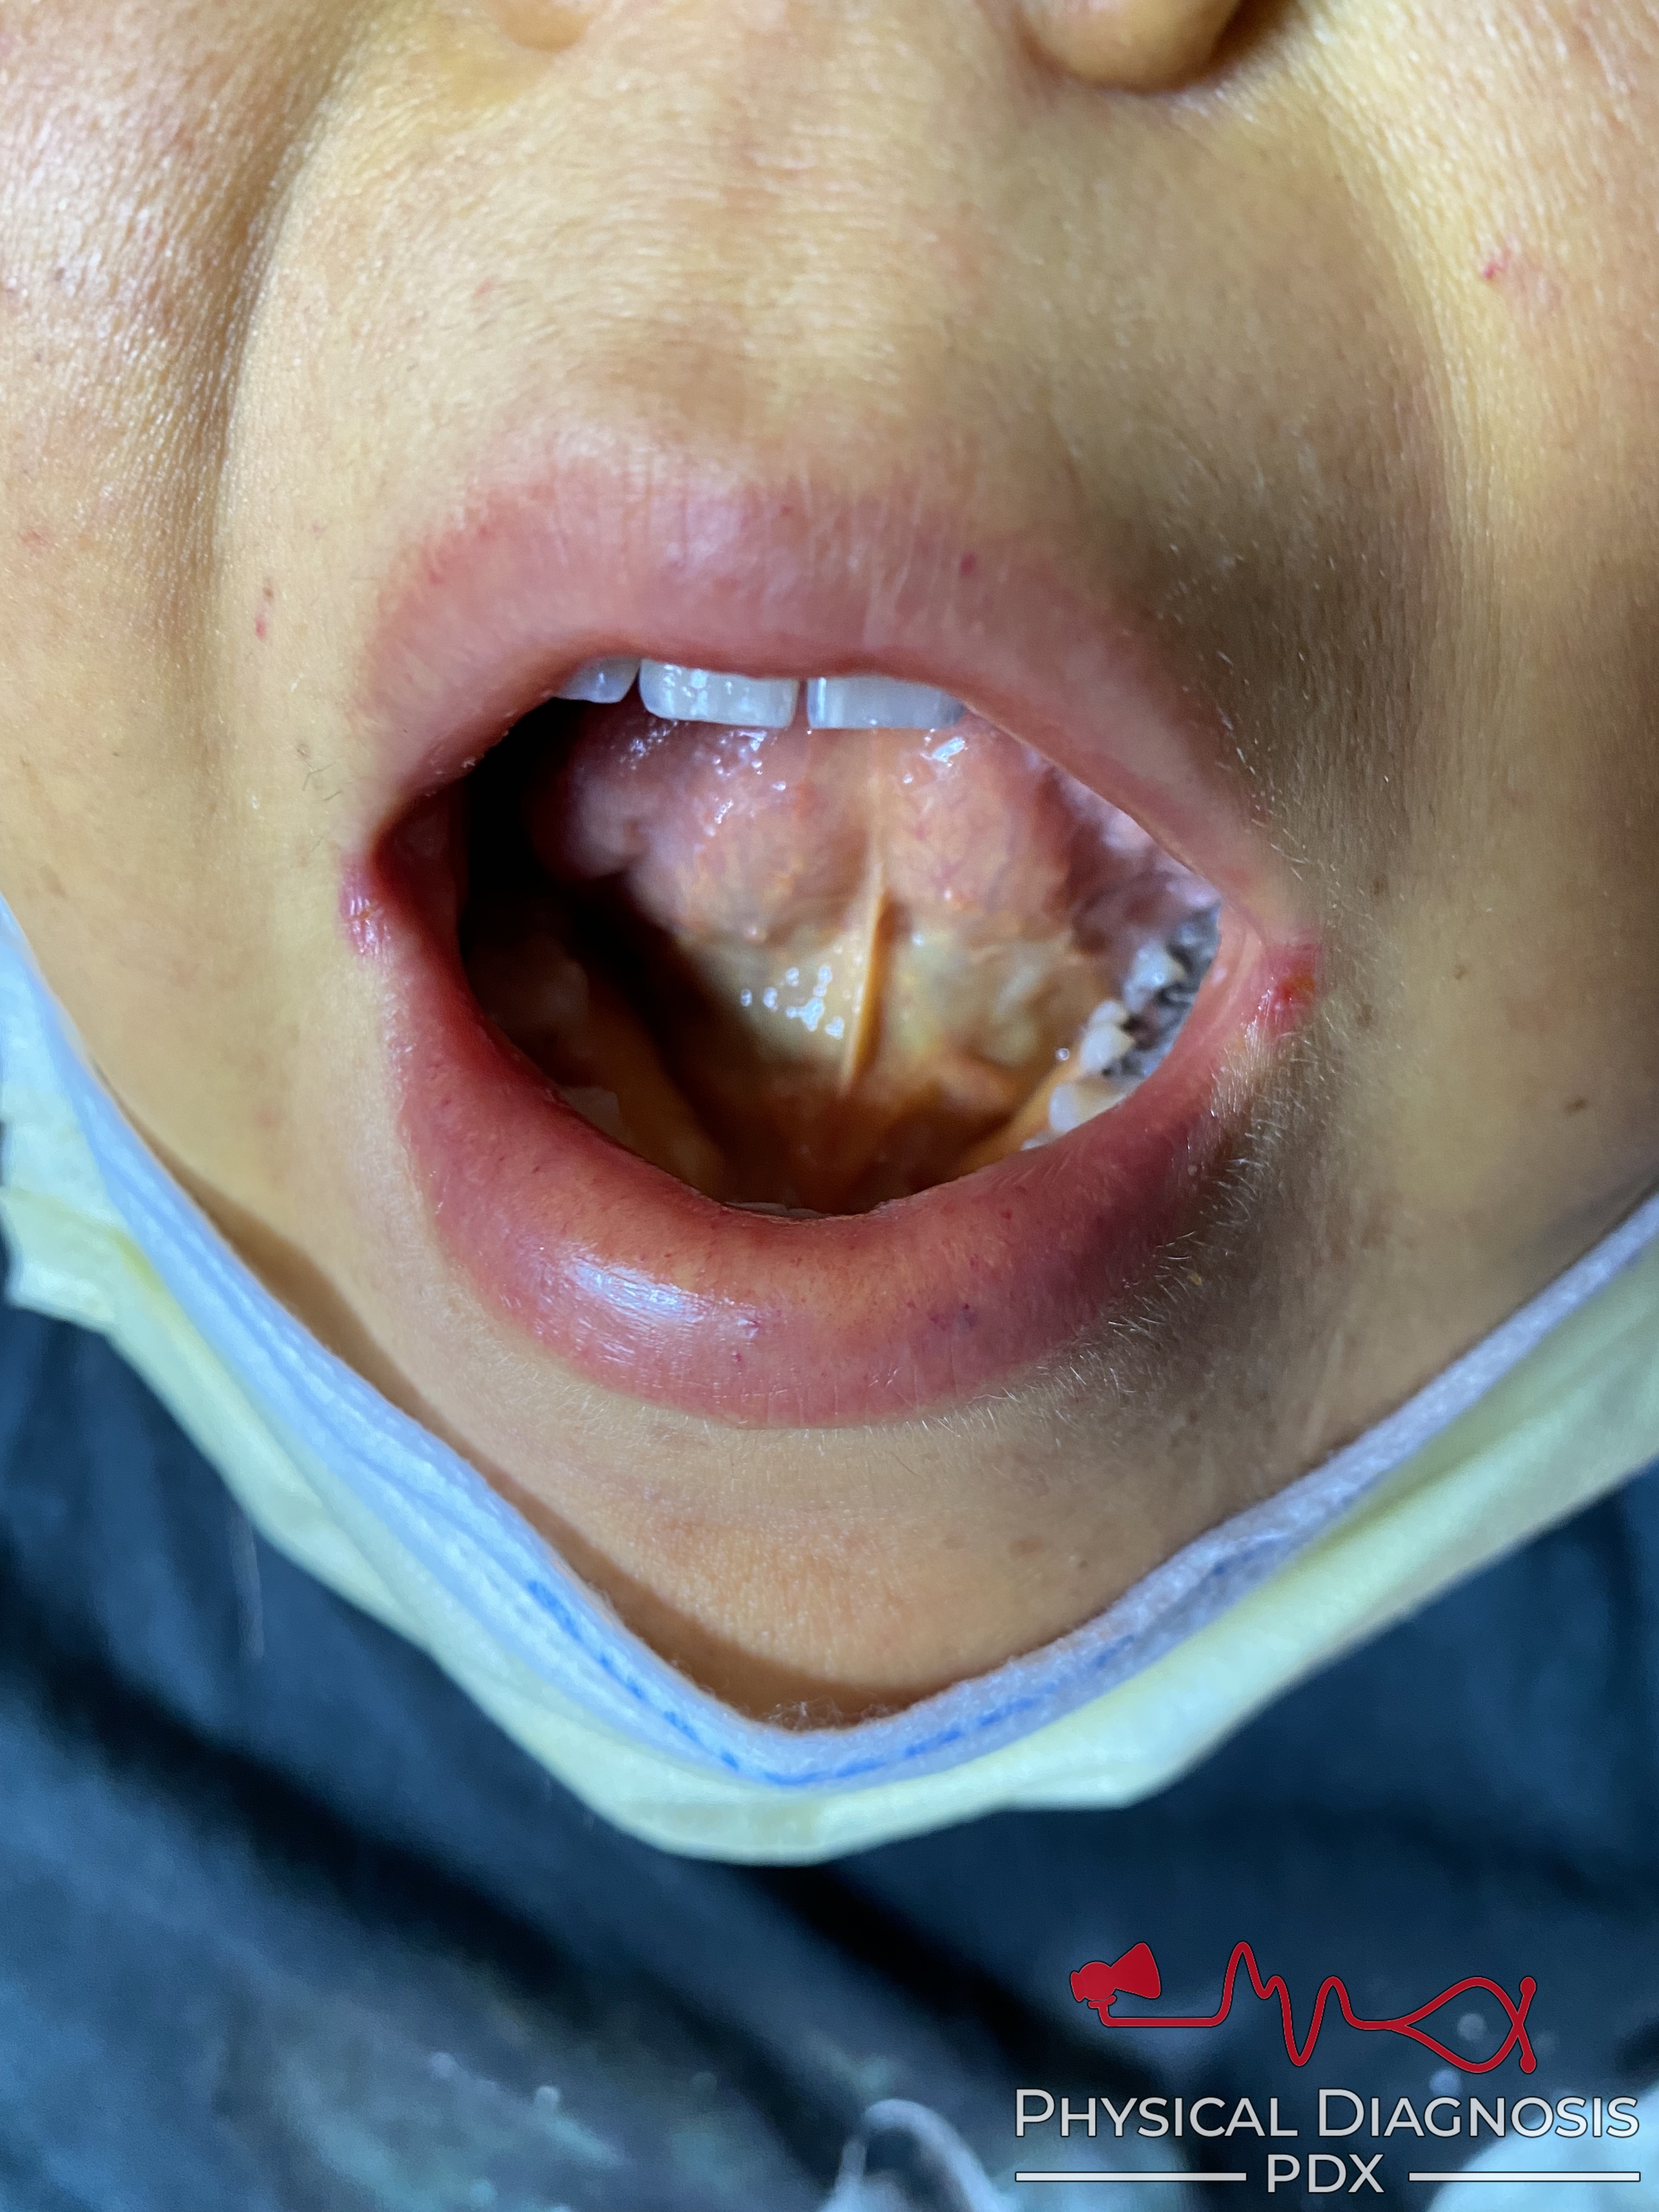

- Can be seen early under the tongue.

Patient 1:

This is a young woman with Laennec’s cirrhosis.

This patient also has spider angiomas and palmar erythema.